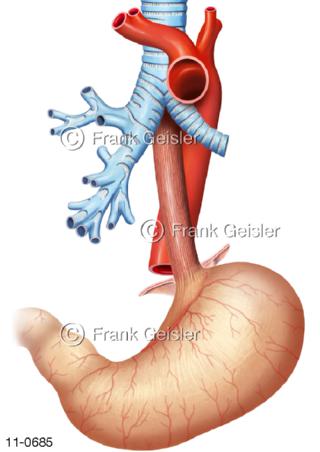

11-0685 Luftröhre Speiseröhre mit Aortenenge Aortenbogen